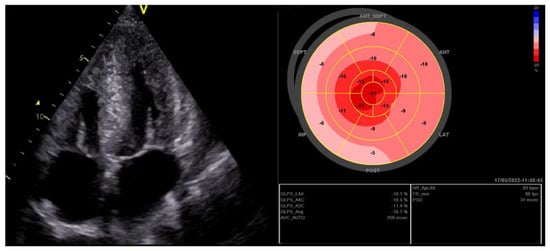

2.1.2. HFpEF